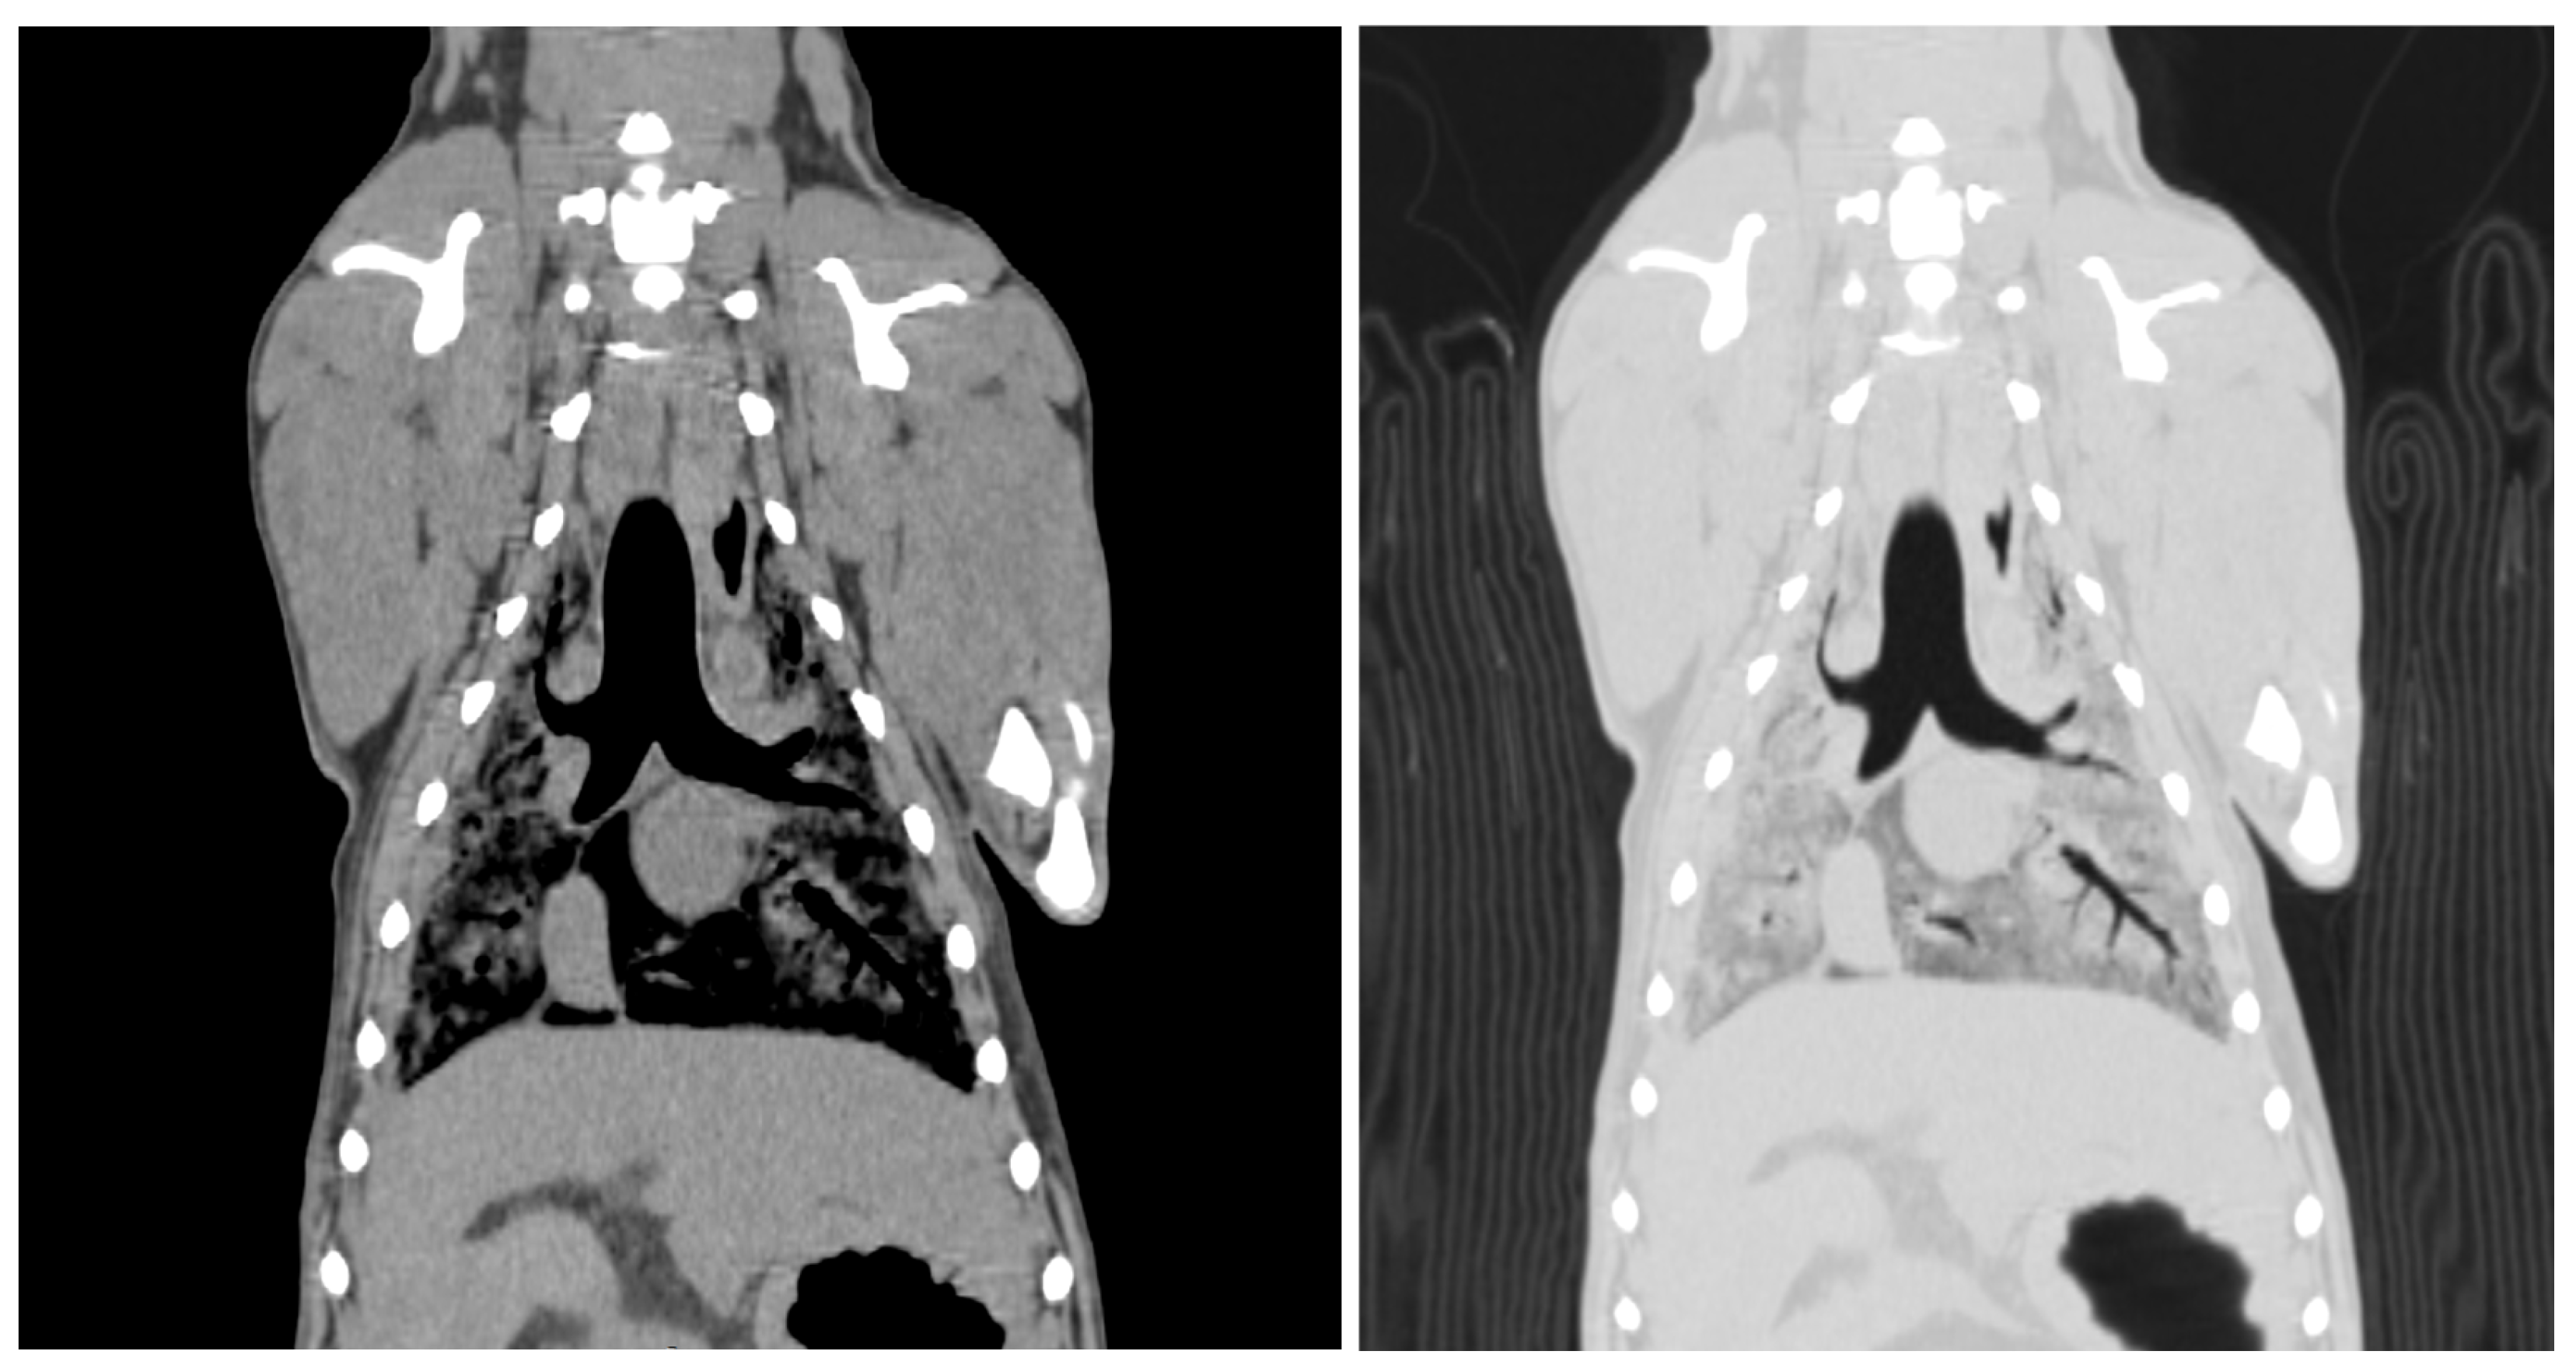

Two readers assessed the image quality of the CT scans. The visibility of the skull and lateral ventricle of the cerebrum in the head region was rated. The visibility of the thoracic structures, including the lung parenchyma, heart, aorta, cranial vena cava, and vertebrae, was scored (Figure 3). The visibility of the aorta, caudal vena cava, liver, kidney, spleen, and vertebrae was assessed.

Figure 3.

Computed tomographic image of the thorax of an SS cadaver 12 weeks after embalming. These images were reconstructed with soft tissue and a lung window. The mean score is 2.50. Lung parenchyma = 1, heart = 3, thoracic aorta = 3, cranial vena cava = 2.5, thoracic vertebra = 3. The scores were assigned as follows; 0 = not visible, 1 = poorly visible, 2 = adequately reproduced, 3 = excellent reproduced.